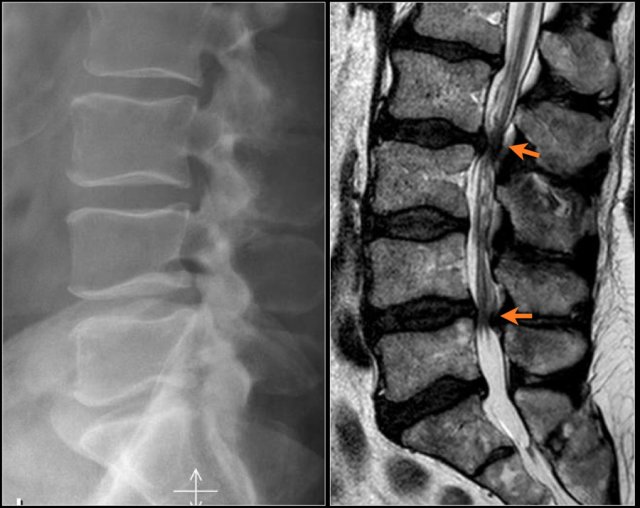

Notice the diffuse narrowing of the lumbar spinal canal.

It is best seen on the MR-images, but can already be suspected on the radiograph, because the pedicles are very short.

You may have to enlarge the image to appreciate this.

On the axial T2W-images you can see, that there is no CSF visible surrounding the nerve roots.

This means that there is a severe spinal stenosis.

Here another example of spinal stenosis.

Again on the radiograph you can suspect congenital narrowing.

Usually a small hernia or bulging is enough to cause nerve compression in these patients.

On the axial T2W-images a severe spinal stenosis is seen.

Notice the short pedicles in combination with facet arthrosis and flavum hypertrophy.